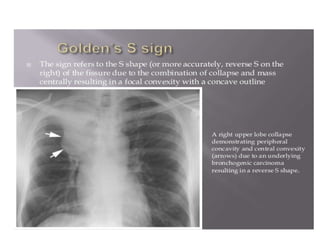

Golden‘s (reverse S)

sign. a. Chest X-ray of a

patient with a centrally

located mass. The

reverse S sign due to

right upper lobe

atelectasis is clearly

depicted. The lateral

portion of the ‘S’ is

formed by the superiorly

displaced minor fissure

and the medial portion by

the mass (arrows). b.

Golden S.

• Golden‘s (reverse S) sign.a. Chest X-ray of a patient with a centrally located mass. The reverse S sign due to right upper lobe atelectasis is clearly depicted. The lateral portion of the ‘S’ is formed by the superiorly displaced minor fissure and the medial portion by the mass (arrows). b. Golden S.